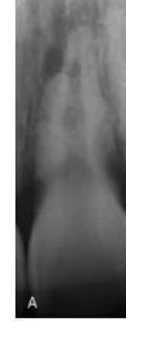

MFD EXAMS /23 6 1234567891011121314151617181920212223 You have 30 min to complete this exam. The timer will start once you begin Attention: Only a few minutes left! Please submit your answers soon. MFD 1 Get a quick sneak peek before the real exam !This trial quiz is designed to show you the question style, difficulty level, and how the options will appear on the platform. 1 / 23 1. What is the lethal dose and toxic dose of fluoride, management? Check 2 / 23 2. What the advantage of silver diamine over other methods and disadvantages ? Check 3 / 23 3. Method of topical fluoride application with concentration ? Check 4 / 23 4. What will happen if left untreated? Check 5 / 23 5. What changes that will happen if the habit stopped? Check 6 / 23 6. Give 3 of your initial stage of treatment? Check 7 / 23 7. What are the causes? Check 8 / 23 8. What is this? Check 9 / 23 9. Then they specified the type of pain and asked about the diagnosis Check 10 / 23 10. What other tests to check vitality of the pulp? Check 11 / 23 11. What are the factors will govern the Rx of Posterior cross bite ? Check 12 / 23 12. What are the factors that govern the treatment of anterior cross bite? Check 13 / 23 13. Name the appliance that you can use to treat this case? Check 14 / 23 14. Name 3 causes? Check 15 / 23 15. Name the most important clinical diagnostic information you need to know. (check RCSI intensive course )? Check 16 / 23 16. What do you see? Check 17 / 23 17. What is your treatment? Check 18 / 23 18. Name the investigations needed? Check 19 / 23 19. causes for gingival enlargement ? Check 20 / 23 20. What is the common side effect of this drug? Check 21 / 23 21. Name the drug that he may take to treat this condition? Check 22 / 23 22. The patient may have what? Check 23 / 23 23. What is this clinical condition? Check /31 2 12345678910111213141516171819202122232425262728293031 You have 30 min to complete this exam. The timer will start once you begin Attention: Only a few minutes left! Please submit your answers soon. MFD 2 Get a quick sneak peek before the real exam !This trial quiz is designed to show you the question style, difficulty level, and how the options will appear on the platform. 1 / 31 1. Mention 2 fixed space maintainers and 2 removable space maintainers other from mentioned : Check 2 / 31 2. Other space maintenance used for child lost primary second molar E before the eruption of the permanent molars ? Check 3 / 31 3. What are the difference between nance appliance and Transpalatal arch Check 4 / 31 4. What material used to attach band? Check 5 / 31 5. What instruction you give to patient? Check 6 / 31 6. Name other fixed space maintainer used in upper jaw and mechanism of their action? Check 7 / 31 7. What component of this appliance? Check 8 / 31 8. What is this appliance , for what its used ? Check 9 / 31 9. Treatment? Check 10 / 31 10. Define Abrasion and Erosion? Check 11 / 31 11. What does this picture show? Check 12 / 31 12. what investigations you can do ? Check 13 / 31 13. Drugs can lead to lichenoid reaction Check 14 / 31 14. What extra oral features in “ Lichenoid reaction )? Check 15 / 31 15. What microscopical features of it ( licheonoid reaction )? Check 16 / 31 16. Definitive diagnosis ? Check 17 / 31 17. Mention type of suggested biopsy ? Check 18 / 31 18. Mention 4 differential diagnosis ? Check 19 / 31 19. Mention 4 questions you will ask the patient ? Check 20 / 31 20. Give 4 intraoral decription of what you see ? Check 21 / 31 21. What the other surgery can be performed to make prothesis? Check 22 / 31 22. Can this tooth stand with fixed prothesis? (in the opg )à taken from Malek file ? Check 23 / 31 23. Radiograph of missing multiple teeth consider it according to Antes law? ON which tooth you will make Abutment ? Check 24 / 31 24. What is Antes law? Check 25 / 31 25. What is best one to use as abutment in fixed prosthesis A or B? Check 26 / 31 26. What relevance of this picture? Check 27 / 31 27. What’s complication of doing surgery in this area floor of mouth? Check 28 / 31 28. Other 2 radiograph needed in diagnosis? Check 29 / 31 29. Give 4 differential diagnosis? Check 30 / 31 30. What can you see ? Check 31 / 31 31. What is the name of radiograph? Check Your score is /30 1 123456789101112131415161718192021222324252627282930 You have 30 min to complete this exam. The timer will start once you begin Attention: Only a few minutes left! Please submit your answers soon. MFD 3 Get a quick sneak peek before the real exam !This trial quiz is designed to show you the question style, difficulty level, and how the options will appear on the platform. 1 / 30 1. Treatment? Check 2 / 30 2. Histopathology? Check 3 / 30 3. Differential diagnosis Check 4 / 30 4. Clinical features’? Check 5 / 30 5. Patient said, this lesion is very frequent, why? Check 6 / 30 6. What are the causes for ulcers? Check 7 / 30 7. Patient have other signs like uveitis ,Genital ulcerations which syndrome he had ? Check 8 / 30 8. Name of the lesion ? Check 9 / 30 9. Mention some TMJ movement ? Check 10 / 30 10. Blood supply ? Check 11 / 30 11. Nerve supply ? Check 12 / 30 12. Which muscles close? Check 13 / 30 13. Action of open and open wide? Check 14 / 30 14. Why it’s Atypical joint ? Check 15 / 30 15. Name of the ligaments ? Check 16 / 30 16. What would be your management? Check 17 / 30 17. Bacteria involved Check 18 / 30 18. Which type of Periodontitis? Check 19 / 30 19. Treatment? Check 20 / 30 20. Histopathology? Check 21 / 30 21. Differential diagnosis? Check 22 / 30 22. Clinical features? Check 23 / 30 23. What are the time frames for making a complaint? Check 24 / 30 24. What are the 3 points related to negligence? Check 25 / 30 25. Who is allowed access to the patient records? Check 26 / 30 26. How to differentiate if it is upper or lower motor neuron lesion? Check 27 / 30 27. Management? Check 28 / 30 28. What are the causes? Check 29 / 30 29. What should you advise the patient to do? Check 30 / 30 30. What is this lesion? Check Your score is /24 1 123456789101112131415161718192021222324 You have 30 min to complete this exam. The timer will start once you begin Attention: Only a few minutes left! Please submit your answers soon. MFD 4 Get a quick sneak peek before the real exam !This trial quiz is designed to show you the question style, difficulty level, and how the options will appear on the platform. 1 / 24 1. What does MRONJ stands for? Check 2 / 24 2. Give definition for MRONJ Check 3 / 24 3. For what medical problems these medications are used? Check 4 / 24 4. Stages of MRONJ 3 Check 5 / 24 5. What’s this appliance? Check 6 / 24 6. At what age is it used? Check 7 / 24 7. What type of malocclusion is it used to treat? Check 8 / 24 8. What changes will produce? (4 options) Check 9 / 24 9. Disadvantages? Check 10 / 24 10. Why is it flabby tissue? Check 11 / 24 11. what is this condition called? Check 12 / 24 12. Causes ? Check 13 / 24 13. Clinical Features ? Check 14 / 24 14. How to avoid it ? Check 15 / 24 15. Management? Check 16 / 24 16. Ideal post length and width Check 17 / 24 17. Definition of Ferrule it’s the Check 18 / 24 18. What is the importance of the ferrule effect ? Check 19 / 24 19. Describe the radiolucency? Check 20 / 24 20. Give 6 differential diagnosis? Check 21 / 24 21. Give 5 radiographical features? Check 22 / 24 22. What is the difference between incisional and excisional biopsy? Check 23 / 24 23. What other 2 plain radiographs we can we can take? Check 24 / 24 24. ALARA? Check Your score is /22 1 12345678910111213141516171819202122 You have 30 min to complete this exam. The timer will start once you begin Attention: Only a few minutes left! Please submit your answers soon. MFD 5 Get a quick sneak peek before the real exam !This trial quiz is designed to show you the question style, difficulty level, and how the options will appear on the platform. 1 / 22 1. . Types of external root resorption? Check 2 / 22 2. The cause of root resorption in the pic? Check 3 / 22 3. How you will treat it? Check 4 / 22 4. What is this probe? Check 5 / 22 5. What is the mark a ? Check 6 / 22 6. What is the mark b ? Check 7 / 22 7. What is the score from the given reading? Check 8 / 22 8. What is the treatment need of the patient according to the score? Check 9 / 22 9. What is the differential diagnosis ? Check 10 / 22 10. Four clinical features of the lesion? Check 11 / 22 11. Treatment ? Check 12 / 22 12. Describe what do you see? Check 13 / 22 13. Causes for it ? Check 14 / 22 14. Treatment ? Check 15 / 22 15. Picture of patient with Anaphylaxis…after taking Check 16 / 22 16. What is diagnosis? - Check 17 / 22 17. What a the signs of Anaphyalxis reactions ? Check 18 / 22 18. What first line of treatment? Dose? Route of Adminstration? Check 19 / 22 19. Other drug used? Check 20 / 22 20. What are expected complications if not treated ? Check 21 / 22 21. What precautions should be made to prevent anaphylaxis reaction ? - Check 22 / 22 22. Name 10 drug in emergency used with their route of Administration and their condition they use in? Check Your score is /36 1 123456789101112131415161718192021222324252627282930313233343536 You have 30 min to complete this exam. The timer will start once you begin Attention: Only a few minutes left! Please submit your answers soon. MFD 6 Get a quick sneak peek before the real exam !This trial quiz is designed to show you the question style, difficulty level, and how the options will appear on the platform. 1 / 36 1. . What are cases that you have to extract the primary tooth? Check 2 / 36 2. D. What are the indications for extraction? Check 3 / 36 3. What are your treatment options? Check 4 / 36 4. Investigations? Check 5 / 36 5. Type of trauma? Check 6 / 36 6. Patient diagnosed with sjorgen syndrome Histology ? - Check 7 / 36 7. Patient diagnosed with sjorgen syndrome Mention four blood investigations ? Check 8 / 36 8. Patient diagnosed with sjorgen syndrome Mention two sites where can we take the biopsy Check 9 / 36 9. Patient diagnosed with sjorgen syndrome How can you differentiate between primary and secondary ? Check 10 / 36 10. Gingival inflammation present in which syndrome Check 11 / 36 11. What is the treatment? Check 12 / 36 12. mention another connective tissue disease that can lead to lesions “ intraorally “ similar to the Lichen planus ? Check 13 / 36 13. what serious complication can arise from Erosive lichen planus ? Check 14 / 36 14. If it was atrophic lesion what histology might be seen ? Check 15 / 36 15. List the histological features of lichen planus ? Check 16 / 36 16. Lichen planus what dose it affect? Check 17 / 36 17. Age group commonly affected ? -ref SAQ Check 18 / 36 18. What are the clinical presentation ‘ types of lichen planus ‘ Check 19 / 36 19. What might you see in patient’s body that has a relation to this lesion? Check 20 / 36 20. What are the differential diagnoses? Check 21 / 36 21. Factors for platelet adhesion? Check 22 / 36 22. What can you see? Check 23 / 36 23. Other 2 process of hemostasis? Check 24 / 36 24. Two diseases in which they increase ? Check 25 / 36 25. Two diseases in which they decrease? Check 26 / 36 26. Medical term when they decrease? And if they increased Check 27 / 36 27. Function Check 28 / 36 28. Life span ? Check 29 / 36 29. From where they arise? Check 30 / 36 30. Normal number? Check 31 / 36 31. What are the function of the guiding plane ? Check 32 / 36 32. The success rate ? Check 33 / 36 33. Mention single extra preparation requirement for Resin bonded bridge in posterior teeth ? Check 34 / 36 34. Mention 5 preparation features of it? Check 35 / 36 35. Give two advantages of it ? Check 36 / 36 36. What’s the name of this prosthesis? Check Your score is /23 1 1234567891011121314151617181920212223 You have 30 min to complete this exam. The timer will start once you begin Attention: Only a few minutes left! Please submit your answers soon. MFD 7 Get a quick sneak peek before the real exam !This trial quiz is designed to show you the question style, difficulty level, and how the options will appear on the platform. 1 / 23 1. If the same scenario but the tooth is subluxated. What is the management? Check 2 / 23 2. Aim of this procedure Check 3 / 23 3. Steps to do this procedure? Check 4 / 23 4. Management? How to asses the vitality of the tooth Check 5 / 23 5. Mention factors that can affect the treatment plan ? Check 6 / 23 6. Identify the Kenneyd’s classification Check 7 / 23 7. Name its parts? Check 8 / 23 8. Uses of Surveyor Check 9 / 23 9. What is this ? Check 10 / 23 10. Criteria for hand piece sterilization Check 11 / 23 11. steps for wrapped instrument sterilization process ( ref : sterilization in SDCEP)? Check 12 / 23 12. What is the difference between sterilization and decontamination? Check 13 / 23 13. Optimal temperature & pressure & time for autoclave? Check 14 / 23 14. Difference between vacuum and non-vacuum autoclave in mechanism? Check 15 / 23 15. Optimum temperature? Check 16 / 23 16. Advantage of vaccum over non vaccum? Check 17 / 23 17. What is the significance of forehead wrinkling? Check 18 / 23 18. What is Ramsy haunt syndrome ? Rx ? and is it LMN or UMN ? Check 19 / 23 19. Enumerate 3 extracranial and intracranial causes for this ? Check 20 / 23 20. What are the branches of facial nerve? Check 21 / 23 21. Why do we suture the eye in a patient with Facial Palsy? Check 22 / 23 22. Differentiate between Upper and Lower Motor Neuron lesions? Check 23 / 23 23. What is shown in photograph? Check Your score is /27 0 123456789101112131415161718192021222324252627 You have 30 min to complete this exam. The timer will start once you begin Attention: Only a few minutes left! Please submit your answers soon. MFD 8 Get a quick sneak peek before the real exam !This trial quiz is designed to show you the question style, difficulty level, and how the options will appear on the platform. 1 / 27 1. Mention 4 diseases you would see in HIV Patients? Check 2 / 27 2. Give 2 differential diagnosis for this lesion? Check 3 / 27 3. Describe the lesion shown in Photograph B? Check 4 / 27 4. What is your diagnosis ? Check 5 / 27 5. Describe the lesion shown in Photograph A? Check 6 / 27 6. Disadvantages of gold ? Check 7 / 27 7. Ideal cement for All Porcelain? Check 8 / 27 8. Which cement would u use for high caries risk patient? Check 9 / 27 9. How much would you prepare for functional and non-functional cusps in Gold Crown? Check 10 / 27 10. what crown would you go for in bruxism patients out of these 3? Check 11 / 27 11. Name the 3 restorations? Check 12 / 27 12. After administering Local Anesthesia and deciding the choice of biopsy. What should be done before biopsying the lesion? Check 13 / 27 13. Name 2 systemic steroids with dosage you would recommend for this patient? Check 14 / 27 14. Name 2 topical steroids with dosage you would recommend for this patient? Check 15 / 27 15. What is your diagnosis? Check 16 / 27 16. Describe the lesion shown in photograph? Check 17 / 27 17. Name 5 options to increase retention and stability in class l Check 18 / 27 18. E. What is the function of the RPI system ? Check 19 / 27 19. What are the 2 disadvantages of the 2 restorations you mentioned? Check 20 / 27 20. What materials are your 2 restorations made of? Check 21 / 27 21. Other than implants what restoration would you place in this patient? Check 22 / 27 22. Which Kennedy’s classification is this? Check 23 / 27 23. Describe your management? Check 24 / 27 24. What may be the patient complaint? Check 25 / 27 25. What are the causes of this? Check 26 / 27 26. Describe what you see in the photograph? Check 27 / 27 27. which 4 examinations would you undertake? Check Your score is /31 0 12345678910111213141516171819202122232425262728293031 You have 30 min to complete this exam. The timer will start once you begin Attention: Only a few minutes left! Please submit your answers soon. MFD 9 Get a quick sneak peek before the real exam !This trial quiz is designed to show you the question style, difficulty level, and how the options will appear on the platform. 1 / 31 1. Describe what you see in the photograph? Check 2 / 31 2. Three other features of this syndrome ? Check 3 / 31 3. What is the medical condition associated with it “? Multiple OKC? Check 4 / 31 4. Where expansion occurs in the OKC ? Check 5 / 31 5. From which cells this lesion arises from? Check 6 / 31 6. What is your diagnosis? Check 7 / 31 7. What is the histopathology of the lesion shown in Histology slide? Check 8 / 31 8. Give 4 differential diagnosis? Check 9 / 31 9. What is the consequence of premature loss of deciduous teeth? Check 10 / 31 10. Identify those appliances and mention one use for each and mode of action? Check 11 / 31 11. What component of appliance no. 3 ? Check 12 / 31 12. How to overcome open bite disadvantage ? Check 13 / 31 13. What are Disadvantages of this appliance ? Check 14 / 31 14. What Ceph changes are expected while using this appliance ? Check 15 / 31 15. What is the construction of Twin Block Appliance? Check 16 / 31 16. What skeletal and dental changes are expected while using this appliance ? Check 17 / 31 17. What is the ideal age to treat this condition >? Check 18 / 31 18. Indications of the Twin Block Appliance? Two Check 19 / 31 19. Name the Appliance used to correct this? Check 20 / 31 20. What is the treatment? Check 21 / 31 21. How to prevent it Check 22 / 31 22. Mention three mechanisms of action of Fluoride? Check 23 / 31 23. What is the disease caused by excess Fluoride? Check 24 / 31 24. What are the risk factors associated with this patient? Check 25 / 31 25. Name the principal organism causing this? Check 26 / 31 26. what are the principles of the access cavity Check 27 / 31 27. What is your diagnosis? Check 28 / 31 28. What are principles of cavity preparation? Check 29 / 31 29. What is your Periapical diagnosis? Check 30 / 31 30. What is your Pulpal diagnosis? Check 31 / 31 31. Which test would you undertake? Check Your score is /21 0 123456789101112131415161718192021 You have 30 min to complete this exam. The timer will start once you begin Attention: Only a few minutes left! Please submit your answers soon. MFD 10 Get a quick sneak peek before the real exam !This trial quiz is designed to show you the question style, difficulty level, and how the options will appear on the platform. 1 / 21 1. Patient is 20 years old Mention two treatment options for this case ? Check 2 / 21 2. Patient is 20 years old What is the long term risk for not treating this case ? Check 3 / 21 3. Name of this appliance in the next picture? Check 4 / 21 4. What is the wire used ? Check 5 / 21 5. For which orthodontic cases this appliance is necessary ? Check 6 / 21 6. Why we use retainer ? Check 7 / 21 7. Describe what you see ? Check 8 / 21 8. Differential diagnosis:- Check 9 / 21 9. Name of those muscles ? Check 10 / 21 10. Name the Extrinsic muscles of the tongue? Check 11 / 21 11. . Which nerves innervate the Extrinsic muscles of the tongue?. Check 12 / 21 12. What is the somatic innervation of anterior 2/3 of tongue? Check 13 / 21 13. Which nerve supplies the posterior 1/3 of tongue?. Check 14 / 21 14. From which Pharyngeal arch posterior 1/3 derived from? Check 15 / 21 15. Mention the intrinsic muscle of the tongue ? Check 16 / 21 16. What is the name of this condition ? name the lesion on the skin ? Check 17 / 21 17. Mention 3 drugs that causing it ? Check 18 / 21 18. 2 infections associated with it Check 19 / 21 19. Mention 2 immediate treatment ? Check 20 / 21 20. Why this condition can be fatal ? Check 21 / 21 21. Which test would you undertake? Check Your score is